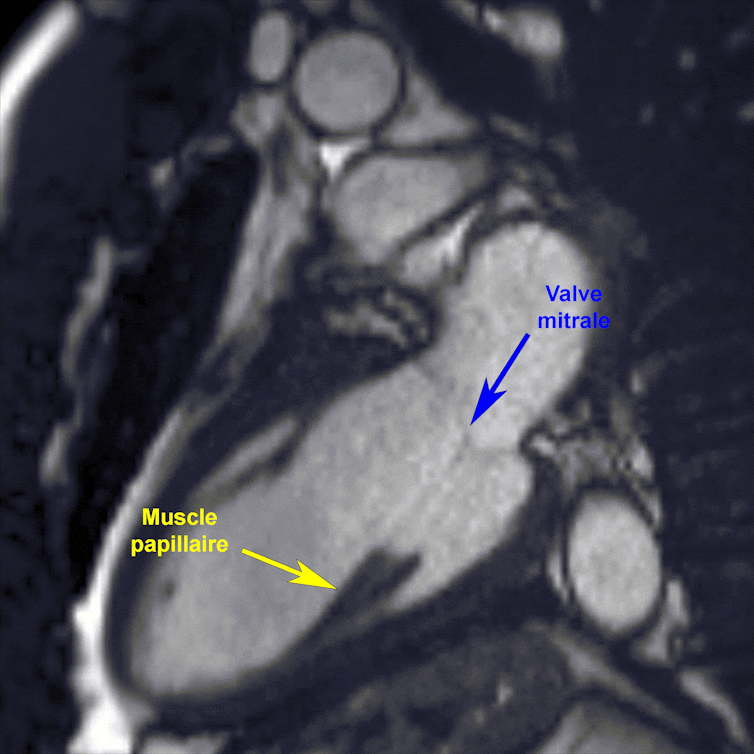

Gif animé du cycle cardiaque du ventricule gauche ; le rythme cardiaque a été ralenti, afin d’avoir le temps d’apprécier la mécanique existant entre le muscle papillaire (indiqué par une flèche jaune) et la valve mitrale (flèche bleue).

Cycle cardiaque du ventricule gauche ; le rythme cardiaque a été ralenti, afin d’avoir le temps d’apprécier la mécanique existant entre le muscle papillaire (indiqué par une flèche jaune) et la valve mitrale (flèche bleue).

Université Libre de Bruxelles, Fourni par l’auteur